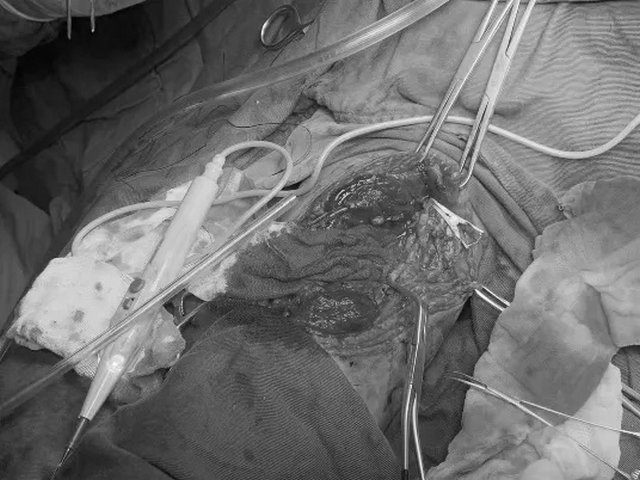

生死时速,患者活动性出血基本控制,外出行CT检查风险高,汇报血管外科崔文军主任医师后同意急诊手术探查。探查发现患者上肢肱动脉离断、肱二头肌离断,桡尺神经损伤,排除骨折情况。

血管外科崔文军主任医师团队予以疮面止血并修复重建离断肱动脉;

骨科樊彦伟副主任医师团队予以修复损伤神经及肌肉、筋膜;

麻醉科胡强夫主任医师团队实施麻醉并予以生命支持。

多学科精诚合作,手术成功完成